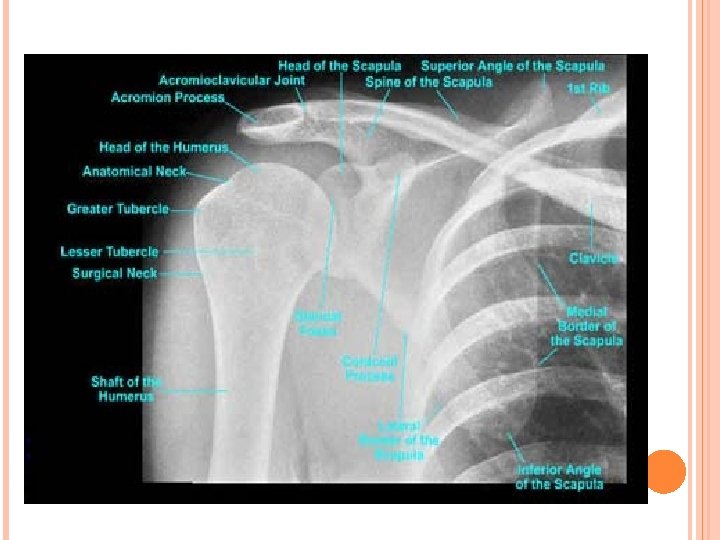

MAJOR BONES OF SHOULDER JOINT Humerus Scapula Clavicle Sternum

HUMERUS Head of the humerus articulates with the scapula’s shallow glenoid fossa Bicipital groove for biceps tendon. It fits between the greater and lesser tuberosity

SCAPULA Glenoid Cavity Situated laterally on the scapula inferior to the acromion and is relatively shallow The glenoid labrum increases the depth of the articulation

SCAPULA Three prominent projections Spine Divides the posterior scapula unequally Supraspinatus fossa and Infraspinatus fossa Acromion Sits at the lateral tip of the spine of the scapula. Tip of the shoulder Coracoid Process “Hooklike Projection” arises anteriorly from the scapula. Curves upward, forward, and outward in front of the glenoid fossa

CLAVICLE S- shaped bone Supports the anterior portion of the shoulder Articulates at tip of shoulder with the acromion and at the sternum near throat

A. Bony Components 1. Clavicle: Collarbone 2. Scapula: Shoulder blade 3. Humerus: Upper arm